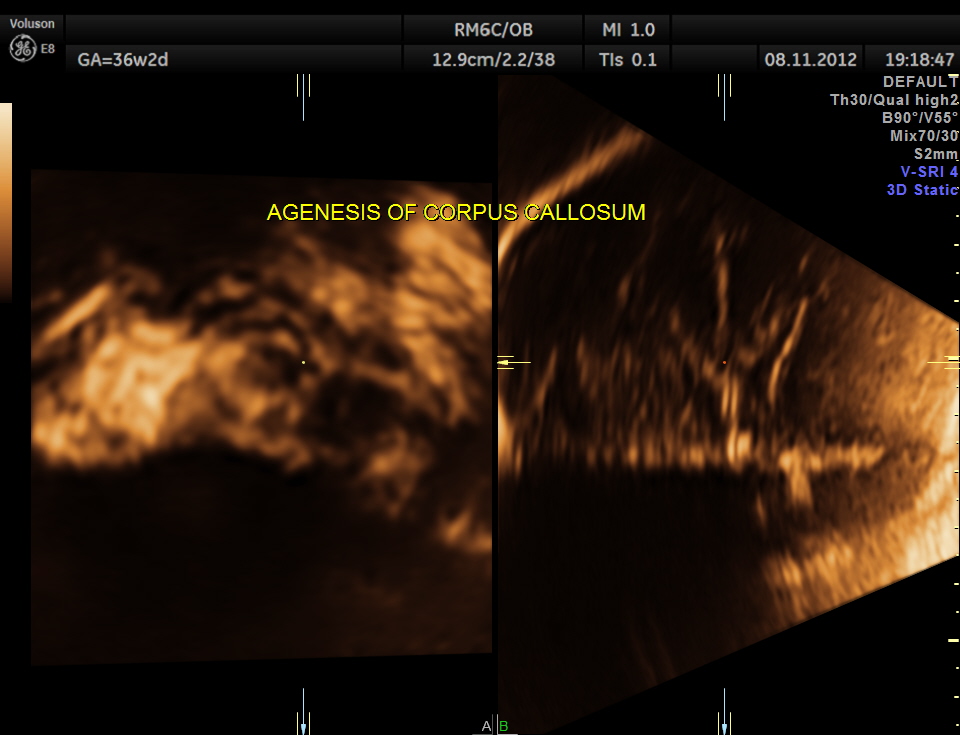

This was a 30 year old primi gravida with no history of consanguinity . This was referred for evaluation of suspected ventriculomegaly.

prominent ventriculomegaly of posterior horns of both lateral ventricles – colpocephaly

demonstration of both medial and lateral ventricular walls at a level where the single periventricular line is normally demonstrated

A specific diagnosis of agenesis of the corpus callosum has seldom been made before the third trimester, probably because the corpus callosum is not normally formed until 18 to 20 weeks43. Most authors agree that detection of agenesis of the corpus callosum is difficult prenatally, depending as it does on postnatal sonograms or CT or MR scans. In a series of seven fetuses with agenesis of the corpus callosum, Bertino et al35 reported that only three demonstrated a characteristic midline cyst. They described three findings that might lead one to suspect agenesis of the corpus callosum on routine transverse views:

- disproportionate enlargement of the occipital horn,

- demonstration of both medial and lateral ventricular walls at a level where the single periventricular line is normally demonstrated, and

- a more parallel course of both ventricular walls than normal.

They suggested that demonstration of these findings on axial views should stimulate additional coronal and sagittal views for evaluation of agenesis of the corpus callosum.

The increased separation of the normal-sized bodies and the enlargement of the atria and occipital horns of the lateral ventricle result in a typical ultrasound image. Upward displacement of the third ventricle is a very specific sign36 but presents only in 40% of fetuses.